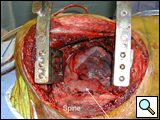

After completion of the spinal procedure, reorientation of the thoracic surgeon by the spinal surgeon is performed, including visualization of the implanted hardware and an explanation of the procedure that was performed (Figures 9a-c). Hemostasis is secured, the chest irrigated, and the posterior mediastinum is inspected for lymph leak (the presence of a CSF leak must be ruled out by the spine surgeon prior to this point in the operation). The diaphragm, if mobilized, is reattached to the fascia of the posterior chest wall with interrupted horizontal 0 prolene sutures or is anchored around the rib. A 28 Fr chest tube is placed in the posterior mediastinum and the chest is closed in a standard fashion. Postoperative spine imaging is necessary to demonstrate adequate position of the hardware and correction of the vertebral defect (Figures 10a-e, Video).

| Figure 9a: Resected vertebral body | Figure 9b: Prosthetic vertebral body placement | Figure 9c: Vertebral fixation plate |